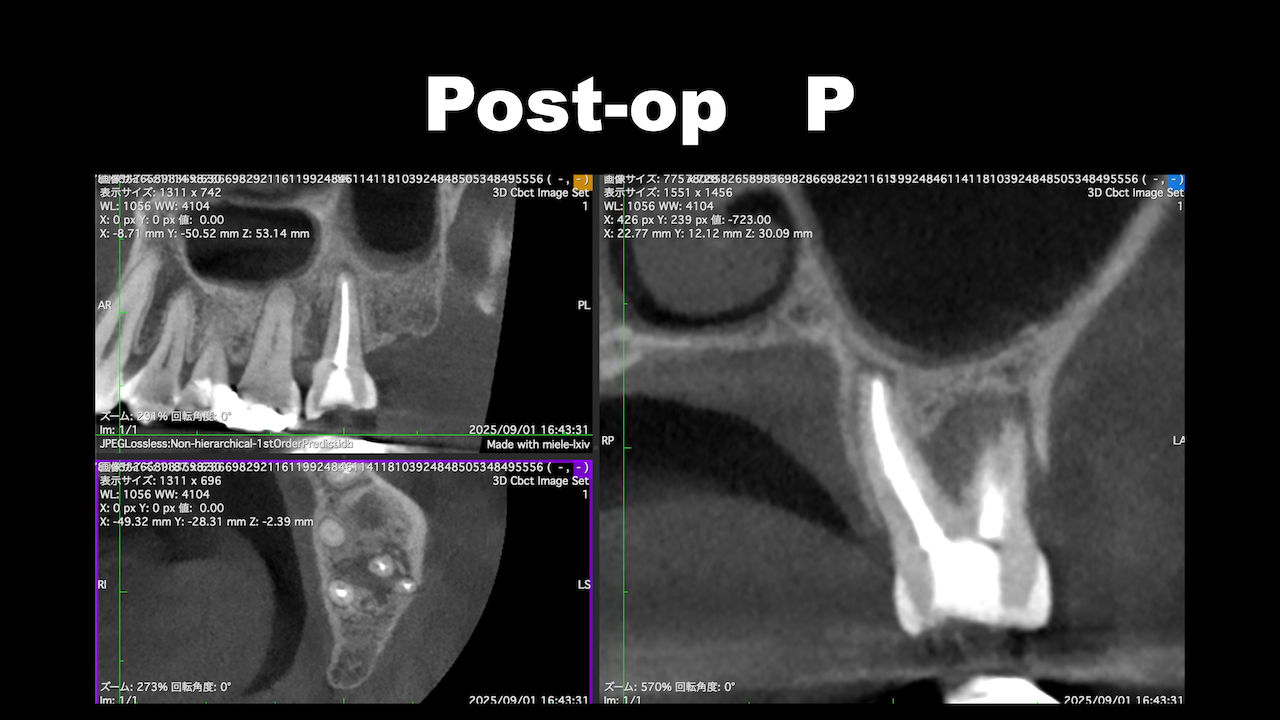

術後にCBCTを撮影するが、

問題はない。